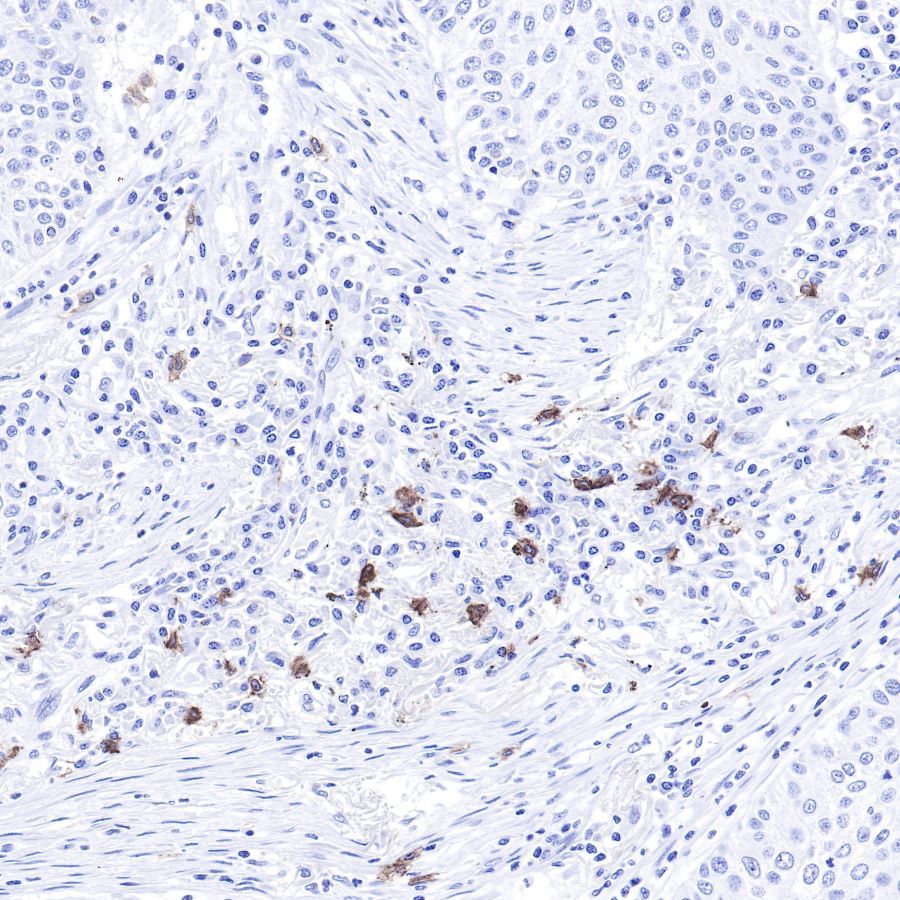

IHC shows positive staining in paraffin-embedded human colon cancer.

Anti-CD117 antibody was used at 1/1000 dilution, followed by a Goat Anti-Rabbit IgG H&L (HRP) ready to use.

Counterstained with hematoxylin.

Heat mediated antigen retrieval with Tris/EDTA buffer pH9.0 was performed before commencing with IHC staining protocol.